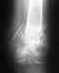

Добрый день! Женщина, 46 лет.Патологический перелом в/3 диафиза плечевой кости. Остеосинтез титановым шрифтом с блокированием.По истечении 1,5 лет рука функционирует в полном объёме. Никаких жалоб.На приёме по поводу удаления шрифта, ортопед предложил нам самостоятельно принять решение, однако заметил, что последние протоколы рекомендуют без особых показаний не прибегать к удалению и оставить все как есть.Как поступить?З.ы. 1. Перелом был признан патологическим на фоне развития множественной миеломы.2. В течении года после операции супруга принимала золендроновую кислоту.3. Наблюдается ремиссия. Противопоказаний к операции у гематологов нет.Спасибо.

Свежие снимки покажите.